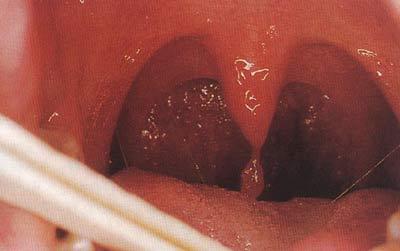

临床诊断为局部上皮增生,系由13或32型人乳头瘤病毒所致的罕见良性

腭裂

悬雍垂过长症的病因

09-07 18:29 关注 腭垂上移到图示那里,没有悬下来